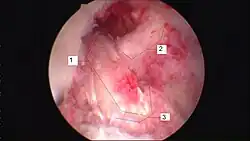

Arthroscopic anterior cruciate ligament (ACL) reconstruction (right knee). The tendon of the semitendinosus muscle was prelevated, folded and used as an autograft (1). It appears through the remnant of the injured original ACL (3). The autograft then courses upwardly and backwardly in front of the posterior cruciate ligament (2).